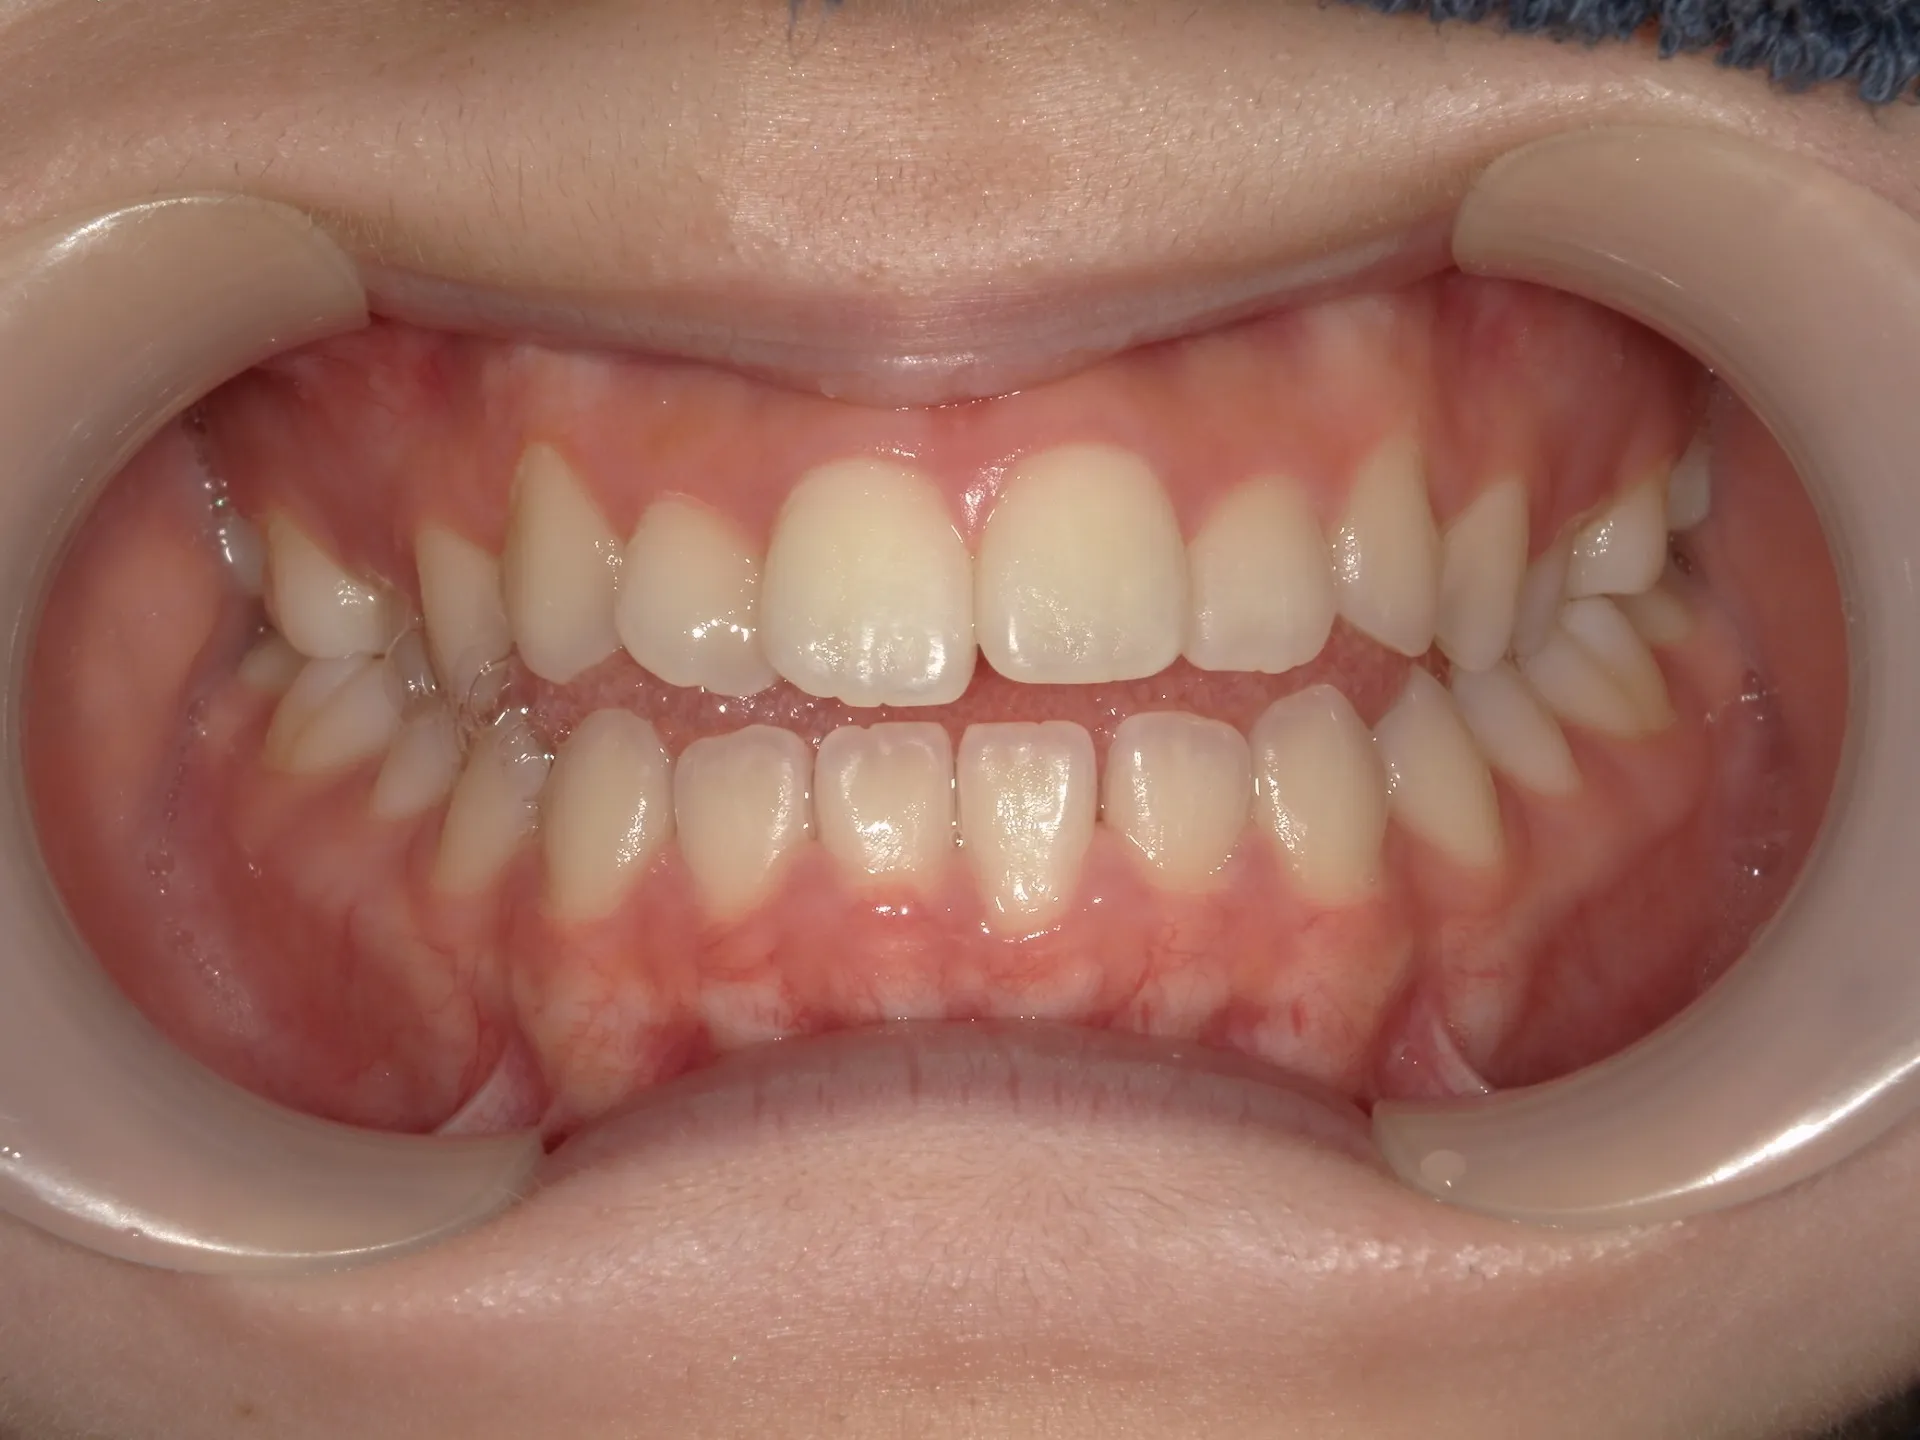

開咬治療後

正面観

治療後の正面観ですが、最初に見えていたスペースは大きく減少していることが分かりますが、左側にはややスペースは残存している状態です。

矯正治療では歯医者が目指すゴールと患者様が考えているゴールはしばしば異なることがあります。

今回は歯医者目線でお話するともう少し矯正を続けた方がよりきれいに機能的になると考えるため矯正治療の続行を提案したいところではあります。